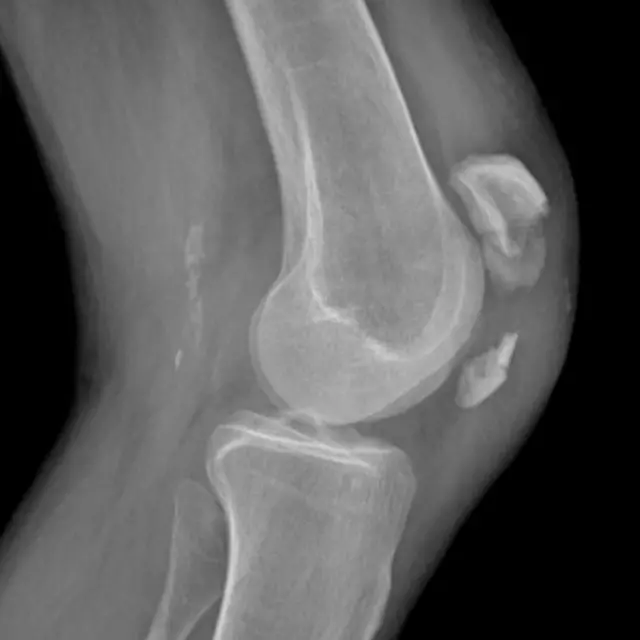

Rodilla

Esta es una lesión del fútbol que puede resultar ser extremadamente seria.

La rodilla es la articulación más compleja del cuerpo, que consta de músculos, ligamentos, tendones y la coyuntura de cuatro huesos. Hay muchas cosas que pueden fallar.

El daño al ligamento medial colateral (LMC) es la más frecuente de las lesiones de la rodilla, aunque los tendones también pueden quedar afectados.

La incidencia de daños al ligamento anterior cruzado (LAC) es relativamente menor, pero los médicos solían forzarte a dejar el fútbol del todo.

Hoy en día, con una exitosa operación y fisioterapia puedes regresar a la cancha en seis meses, aunque podría tomarte mucho más tiempo antes de que te sientas completamente confiado en la estabilidad de tu rodilla.